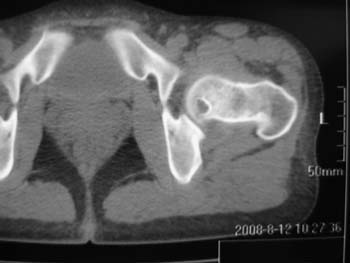

以下是引用358450m在2008-8-12 12:12:00的发言:[br]骨囊肿

以下是引用yangyudong333在2008-8-12 14:30:00的发言:[br]考虑退京变所致关节面下骨质囊变

以下是引用随光逐影在2008-8-12 20:40:00的发言:[br]考虑邻关节骨囊肿或骨内腱鞘囊肿。